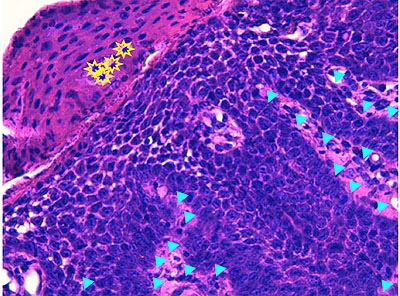

Photo 4 (Hémalun Eosine X 100) : aspect bleu de l’épiderme pour hyperplasie des couches basales, qui dessinent des crêtes épithéliales allongées, filiformes, ramifiées et branchues, peuplées de cellules basales hyperbasophiles. L’épiderme est multifocalement exulcéré. L’infundibulum folliculaire visible présente une hyperkératose parakératosique sans visualisation nette d’une couche des grains. Le derme montre une discrète angiectasie des capillaires du plexus superficial ainsi qu’un discret infiltrat inflammatoire périvasculaire superficial.

Légendes de la Photo 4 :

- Triangles bleus foncés : contours de crêtes épithéliales allongées, filiformes, ramifiées et branchues, peuplées de cellules basales hyperbasophiles.

- Triangles bleus clairs : exulcération épidermique

- Flèche rouge : parakératose épidermique et folliculaire

- Étoile rouge pleine :Le derme est faiblement à modérément inflammatoire (infiltrat mononucléé)

- Étoile rouge creuse : angiectasie des capillaires sanguins

- Étoile bleue claire : glandes sébacées